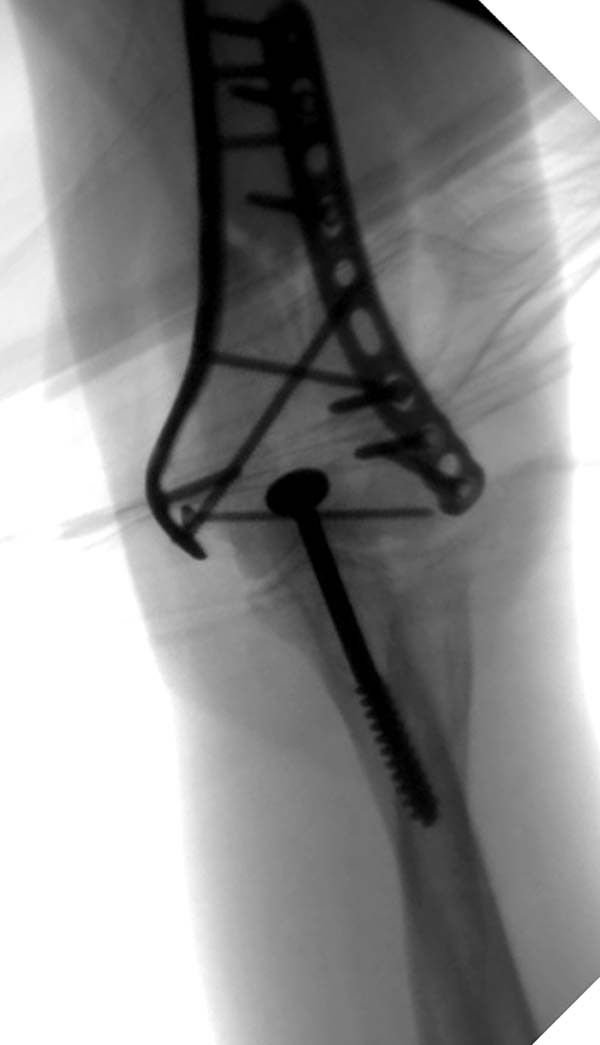

Здесь открытый перелом, временный наружный фиксатор и окончательная фиксация пластинами. Второй случай фиксация без остеотомии отростка пластинами Biomet-DePuy...